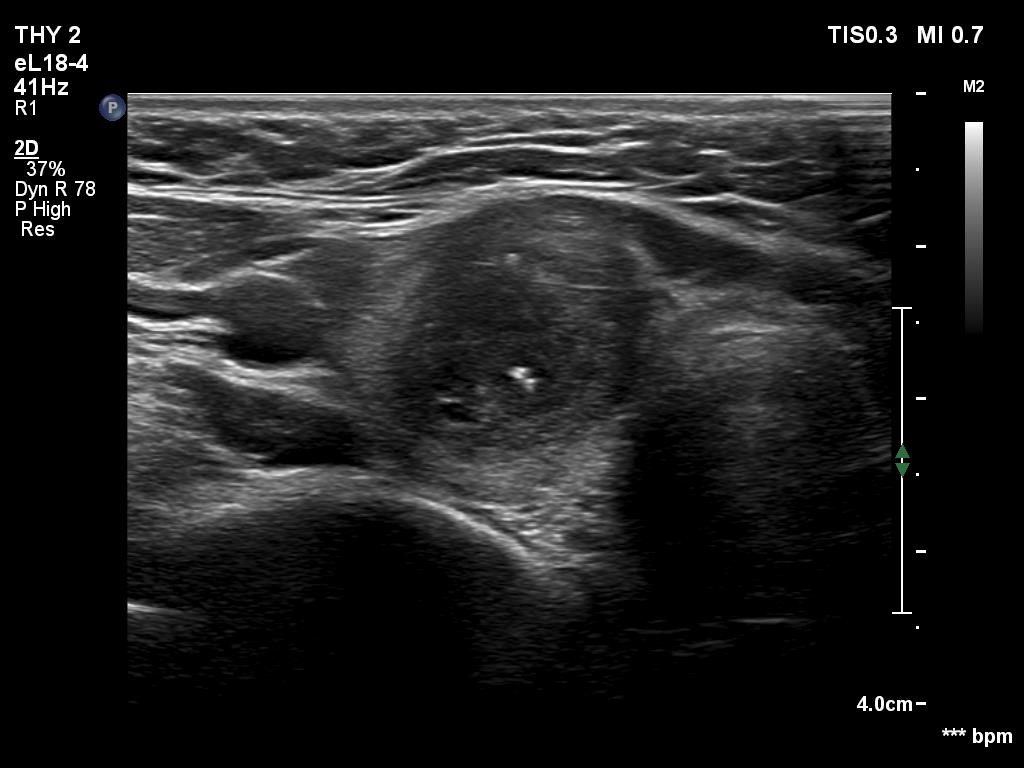

Ultrasonography revealed an echonormal thyroid. There was dominantly moderately hypoechoic nodule in the right lobe. Some parts of the lesion were deeply hypoechoic, and a few small cystic chambers were also within. The nodule presented with irregular shape and borders and had intranodular echogenic figures, primarily granules.

It is ambiguous how to interpret the echogenic figures. Although the presence of irregular shape and borders increases the likelihood that the echogenic granules are indeed microcalcifications, comet-tail artifacts must be also considered.

It is worth comparing the images recorded by using different settings. By using harmonization, we lose the details of very hypoechoic areas. Essentially, the latter seem to be anechoic.